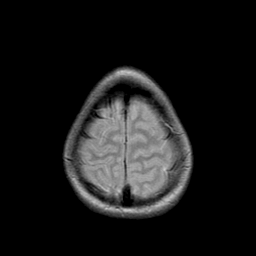

Metastatic bronchogenic carcinoma: proton density-weighted MR -- Slice #20

[Home][Help][Clinical] Slice 20